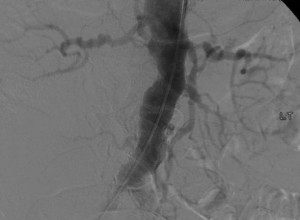

- Angiography – Angiography is the “gold standard” for detection of fibromuscular dysplasia. It can detect lesions as small as 200-300 micrometers. Angiography has the advantage of assessing lesions with IVUS and pressure measurements. Only these internal measurements can truly assess disease severity. However, they are only rarely needed from a clinical standpoint.

The mainstay of treatment for renal artery fibromuscular dysplasia is catheter based balloon angioplasty. Stents are usually not used during angioplasty for renal FMD, unless there is a suboptimal result or dissection. Technical success rate of angioplasty is above 85% and in most cases well over 90% as well. If disease recurs, another PTA is often successful. There is no need to re-intervene unless hypertension or renal dysfunction / reduction in size develop. Return of renal artery stenosis alone is not reason for repeat intervention. If percutaneous treatment fails there is also a surgical option. Renal angioplasty is most successful in treating reno-vascular hypertension in FMD patients who are younger than 50, do not have atherosclerosis of the coronary arteries and have relatively new onset hypertension. The bottom line is that renal artery angioplasty can cure reno-vascular hypertension that is secondary to FMD.